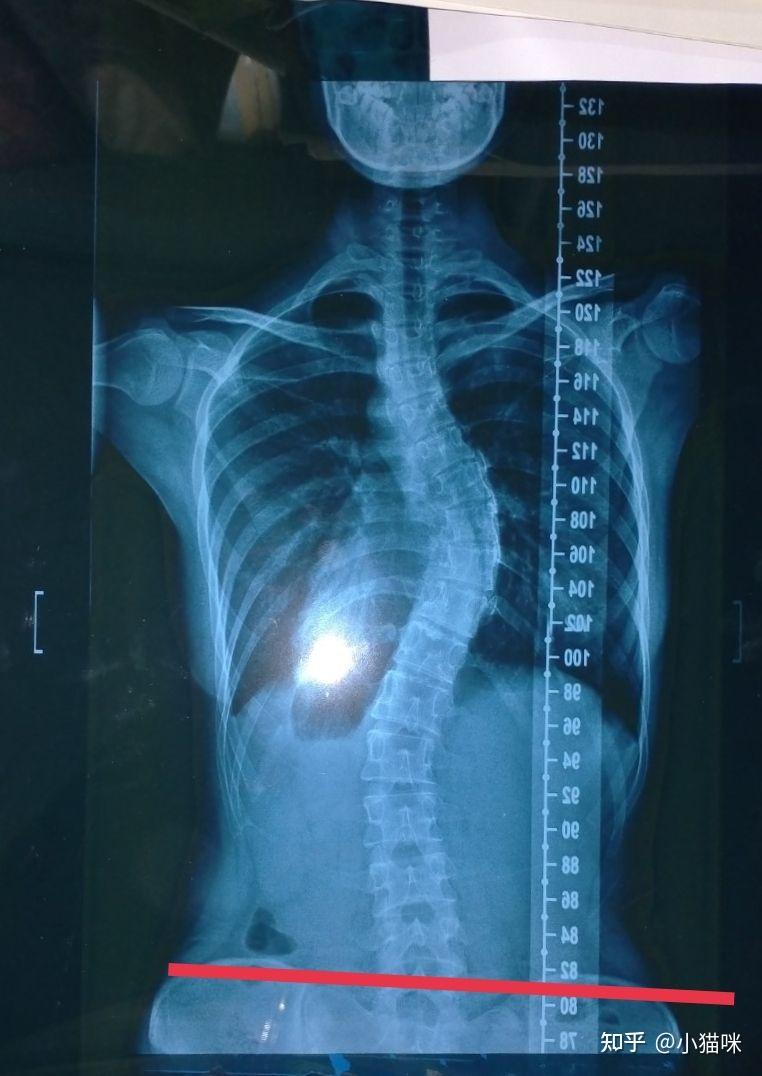

植骨融合术(t1-9)诊断:先天性脊柱侧凸站立位全脊柱正侧位:胸椎右侧弯

今天给大家分享一个腰椎左凸胸椎右凸的案例,如何在躺着的时候进行

案例中的小咪还处于青春期,侧弯度数超过20°,佩戴德国gbw支具之后